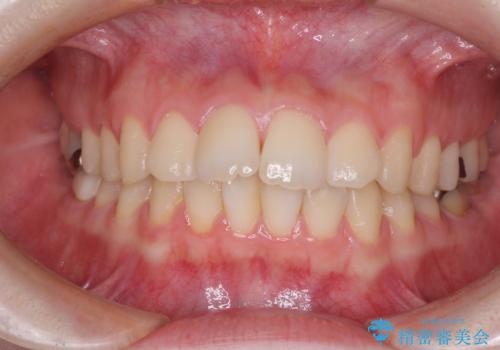

[前歯のねじれ・がたつきを治したい ]ワイヤーとマウスピースの併用矯正治療

![[前歯のねじれ・がたつきを治したい ]ワイヤーとマウスピースの併用矯正治療の症例 治療前](https://seimitsushinbi.jp/wp/wp-content/uploads/2023/11/IMG_0010-1-500x350.jpg?v=1699509973)

![[前歯のねじれ・がたつきを治したい ]ワイヤーとマウスピースの併用矯正治療の症例 治療後](https://seimitsushinbi.jp/wp/wp-content/uploads/2023/11/1c93ab7139a768f1f61b6dd35aac7324-500x350.jpg?v=1699510065)